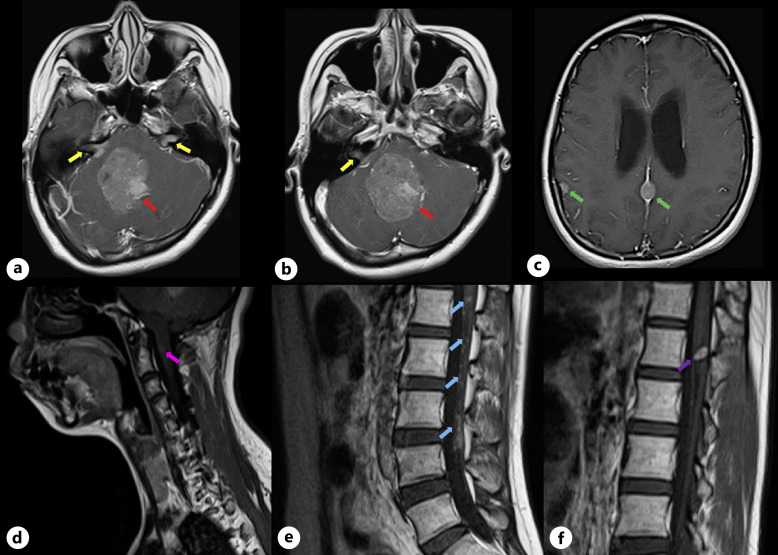

Introduction: NF2-related schwannomatosis (NF2) is a rare inheritable autosomal dominant disorder characterized by multiple nervous system neoplasms.

Case presentation: In this report, we present a rare case of NF2 exhibiting the complete constellation of multiple inherited schwannomas, meningiomas, and ependymomas (MISME syndrome).

Conclusion: This is the first documented case of simultaneous occurrence of all three tumors in a single patient in the Philippines, adding to the sparse evidence of MISME syndrome in world literature.